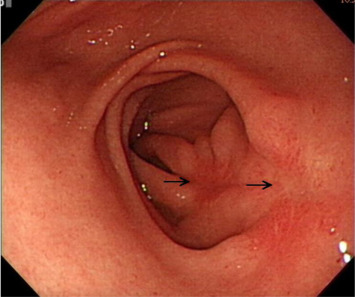

The histopathological examination from both resected specimens showed nests of HP tissue in the submucosal layer (Fig. 6 ). Although the margins of the resected specimens were not free of HP tissue, her EGD at follow-up 2 months later showed only two linear ulcer scars on the previous EMR sites without endoscopic evidence of a residual protruded lesion (Fig. 7 ).

Esophagogastroduodenoscopy at follow-up shows two linear ulcer scars (arrows) ...

Figure 7.

Esophagogastroduodenoscopy at follow-up shows two linear ulcer scars (arrows) without endoscopic evidence of a residual protruded lesion.